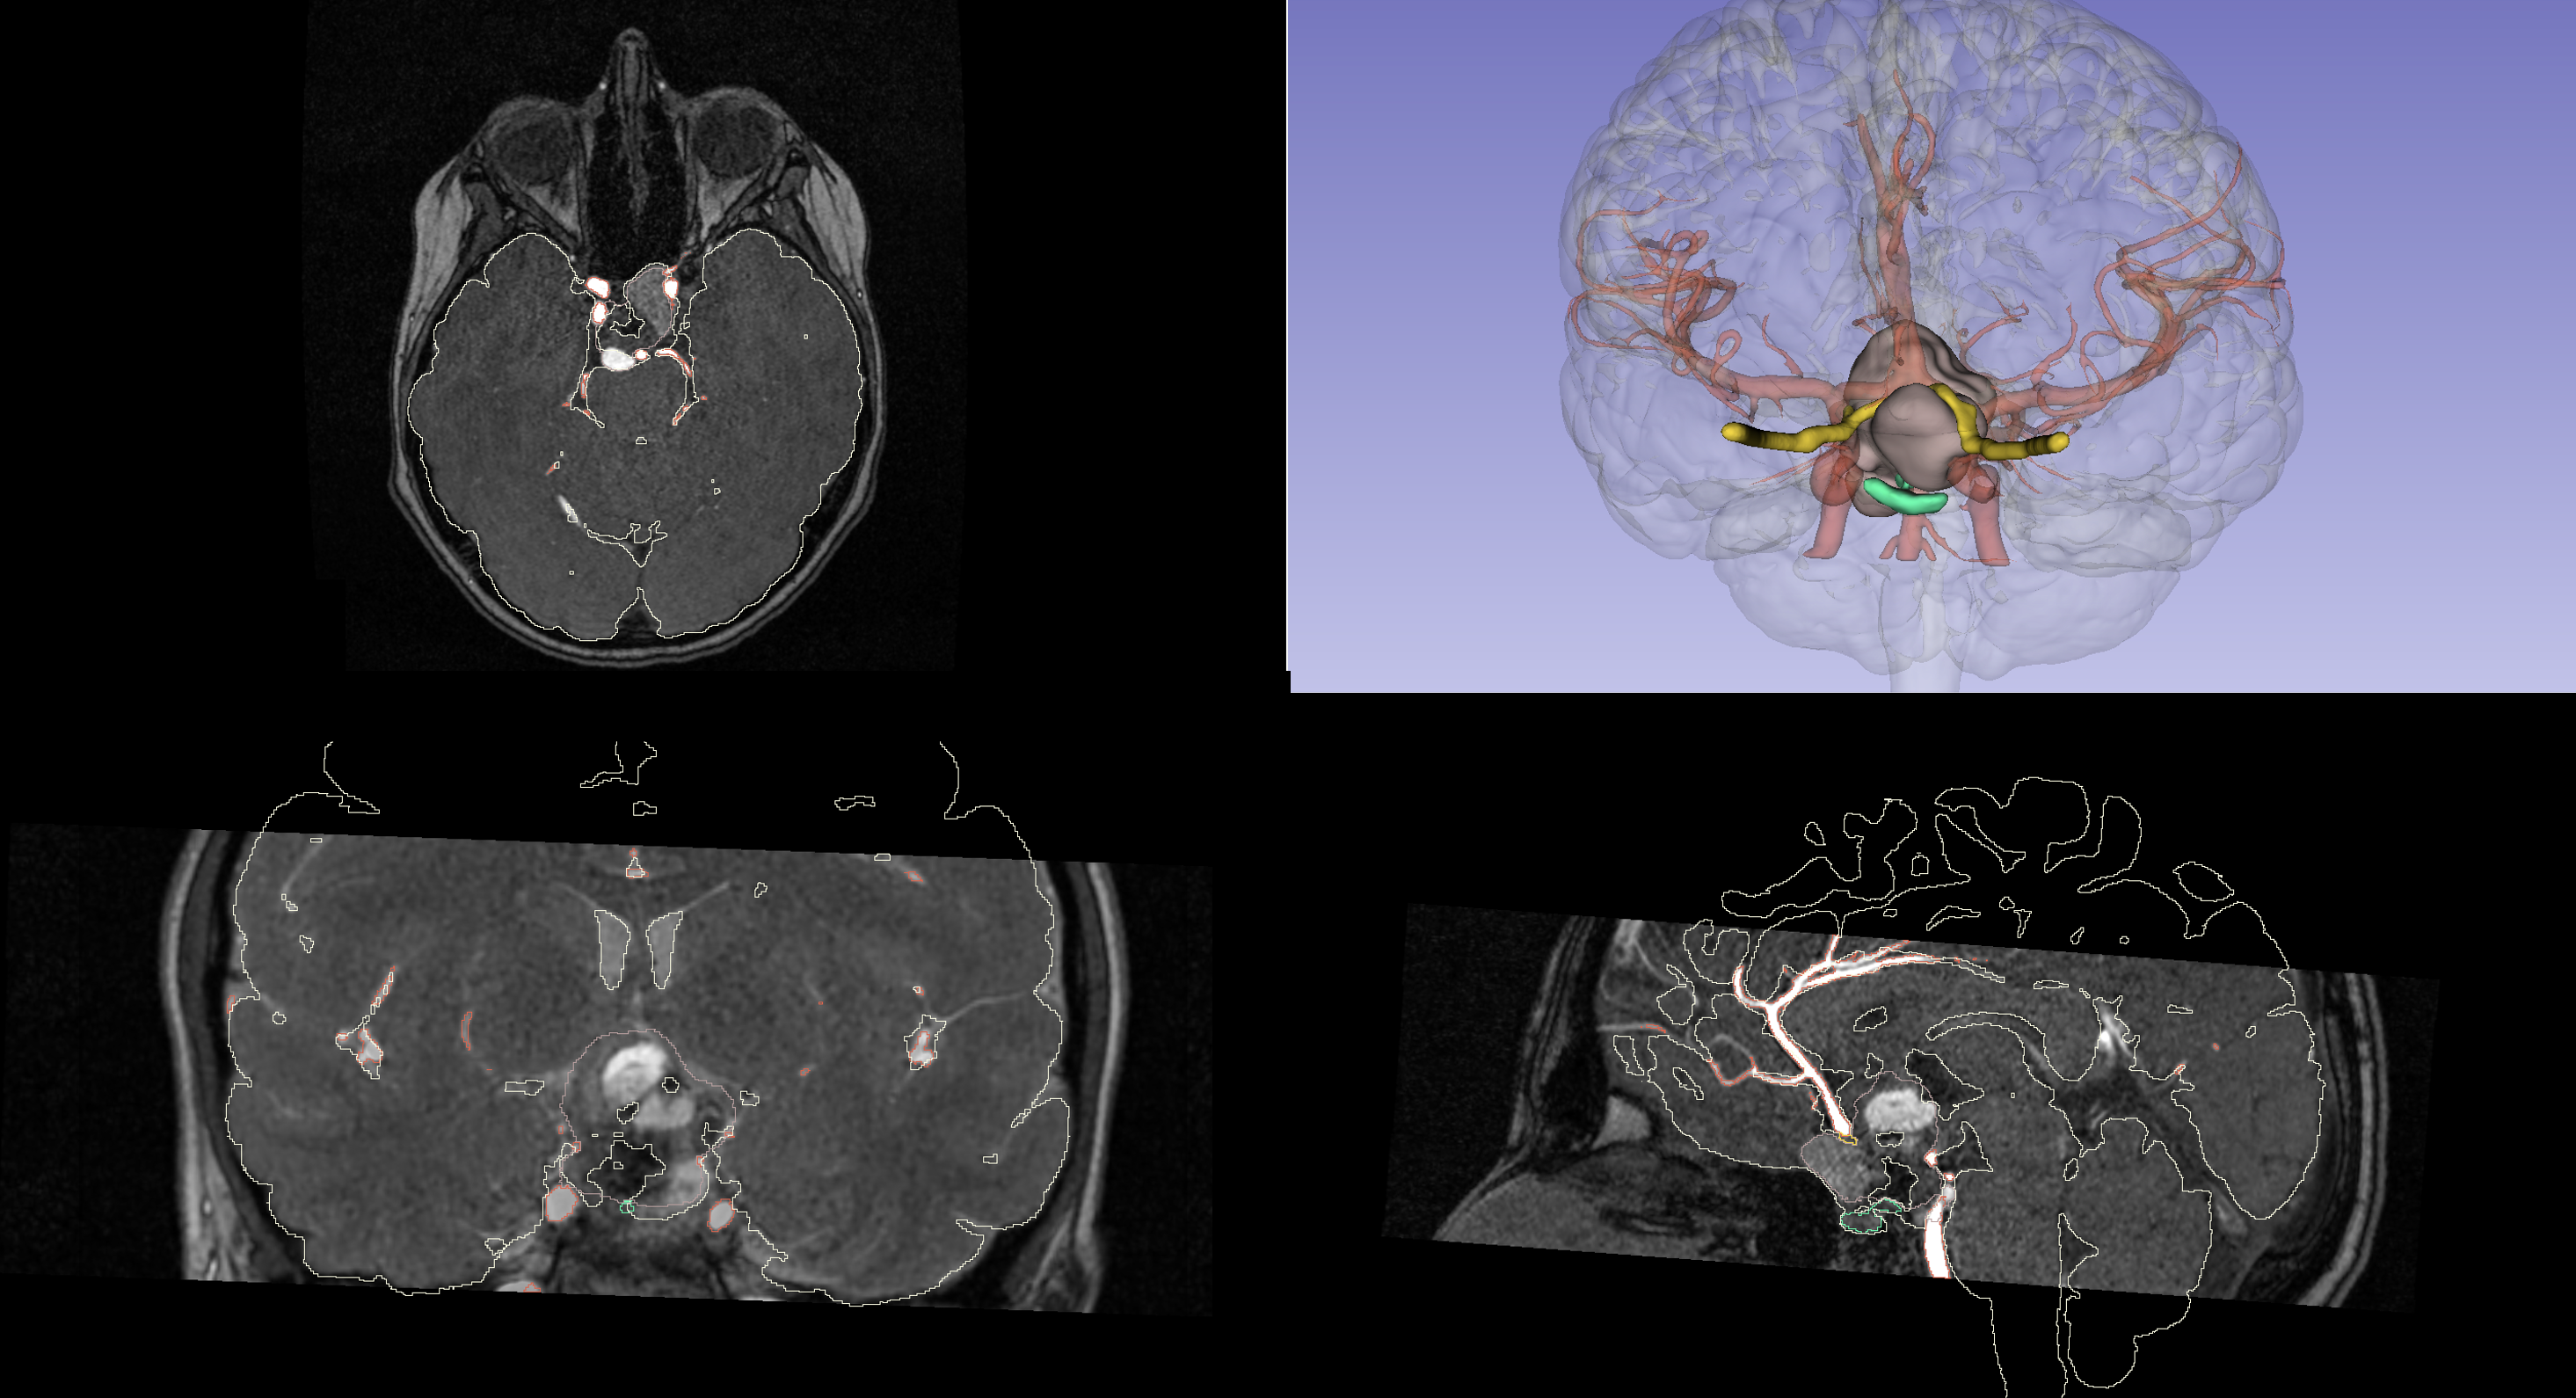

We are pleased to share a new scientific contribution that explores a multidisciplinary and technologically advanced approach to the treatment of pediatric craniopharyngioma—a rare benign tumor of the hypothalamic–pituitary region, often associated with high morbidity. This work stems from the long-standing collaboration between PRINTMED 3D and the “Vittore Buzzi” Children’s Hospital in Milan, and stands as a concrete example of how synergy between clinical practice and research can generate effective, personalized solutions for pediatric neurosurgery.